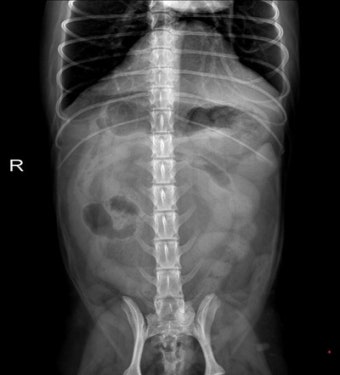

장난감 조각, 뼈 조각, 플라스틱 같은 이물질을 삼켰을 경우 몸이 그것을 배출하려고 구토를 유도합니다. 이때는 억지로 빼려 하기보다는 병원에서 X-ray 촬영이 필요합니다.